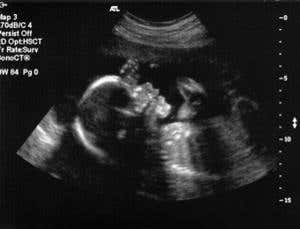

Surgery in the womb is now routine Oleksiy Maksymenko/Getty

Flake has been performing surgery on unborn babies for nearly 30 years, using techniques refined on pregnant animals to ensure they met the challenges of working on tiny bodies and avoided triggering miscarriage. The first operation on a human fetus took place in 1981 to fix a blocked urethra, the tube that carries urine out of the bladder. Since then the field has grown to encompass many types of surgery, such as correction of spinal cord defects to prevent spina bifida.